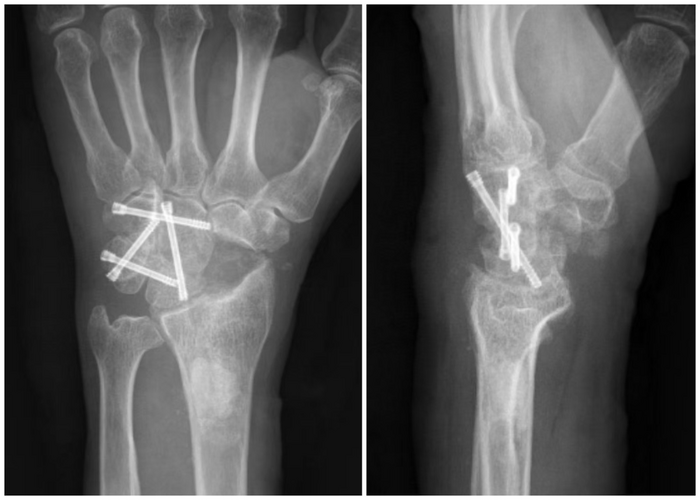

患者的困境与求医之路 该患者是一位农民,靠双手养家糊口。然而,命运却跟他开了个残酷的玩笑,腕关节的疼痛逐渐成为他生活与劳作的巨大阻碍。起初,腕部的不适只是偶尔闪现,他并未太过在意,以为只是劳作后的疲劳反应,简单休息后便又继续田间的忙碌。但随着时间推移,疼痛愈发频繁且剧烈,不仅影响到他日常的农活,连简单的抬手、握拳动作都变得异常艰难,夜晚更是常常被腕部的刺痛惊醒。 在家人的劝说下,他踏上了求医之路。辗转多家医院后,经X线片和MRI检查,最终被确诊为舟月分离导致的SLAC腕四期病变。这一病症使得桡舟关节、头月关节、钩头关节均出现严重关节炎,软骨剥脱,软骨下骨外露,腕关节的正常结构与功能遭受极大破坏,若不及时治疗,手部功能将进一步恶化,甚至可能面临残疾的风险。 传统切开手术存有局限 面对如此复杂棘手的病症,传统的切开手术曾是主要治疗手段之一。传统切开手术需要在腕关节处切开较大的切口,以充分暴露病变部位,这就如同对腕关节进行了一场“大刀阔斧”的拆解。一方面,大面积的切口意味着要切断诸多周围的软组织、韧带等结构,术后极易引发局部粘连,严重影响关节活动度,让患者在术后康复过程中面临漫长而艰难的功能锻炼阶段,且效果往往不尽如人意。另一方面,切开手术创伤大、出血多,术中视野相对有限,对于一些细微病变的处理难以做到精准到位,就好比在昏暗灯光下进行精细的雕刻工作,容易遗漏一些隐藏较深的病灶,增加了手术风险与术后复发的可能性。 腕关节镜下 四角融合术优势尽显 烟台山医院付胜强主任团队深知传统手术的弊端,在经过严谨的病例讨论与术前评估后,决定为患者实施腕关节镜下四角融合术。 手术当日,在精心的术前准备后,患者被推进手术室。与传统手术大开大合的场面截然不同,腕关节镜手术仅通过几个微小的切口,便将纤细的关节镜及手术器械探入腕关节内部。关节镜宛如医生的“第三只眼”,将腕关节内的病变情况清晰地呈现在屏幕上,细微之处纤毫毕现,为手术提供了精准的“导航”。 术中,付胜强主任熟练地操作关节镜,使用精细磨头、髓核钳等特制工具,透过微小切口直达病灶。在清除病变的舟骨时,犹如在狭窄的管道内进行一场精细的微雕手术,精准地去除病变组织,最大限度保留了健康的骨与软组织,将手术创伤降到最低。随后,对各个病变关节面的处理更是有条不紊,依次暴露并清除头月、钩头、月三角、钩三角各关节对应软骨面,操作精准度远超传统手术。 克氏针固定各关节环节,如同搭建稳固的“脚手架”,为后续置入3.0 空心加压螺钉奠定坚实基础。每一步操作都在关节镜的实时监控下进行,术中拍片再次确认固定位置良好,确保每一枚螺钉都精准就位,为腕关节的融合与康复提供可靠保障。 相较于传统切开手术,此次腕关节镜下四角融合术优势显著: 从创伤层面看,微小切口极大减少了对周围组织的破坏,术后切口愈合快,疤痕微小,几乎不影响腕部外观。周围软组织、韧带等结构得以完整保留,有效避免了术后粘连的发生,为患者术后快速康复、恢复手部功能创造了有利条件。 出血少是另一大突出优势,术中几乎看不到大量出血的场景,这不仅降低了因失血过多引发的各类风险,也减少了术后输血的可能性,减轻了患者身体负担,让患者在术后能以更快的速度恢复体力,投入到后续康复训练中。 精准度更是腕关节镜手术的“王牌”。凭借高清的关节镜视野,医生能够清晰辨别正常组织与病变部位,对病灶的清除做到“斩草除根”,同时避免误伤到周围重要结构,大大提高了手术治疗效果,降低了术后复发风险,让患者吃下“定心丸”。